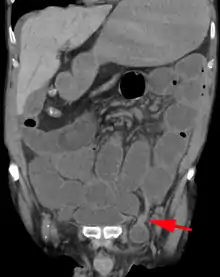

A physician may diagnose an inguinal hernia, as well as the type, from medical history and physical examination.[20] For confirmation or in uncertain cases, medical ultrasonography is the first choice of imaging, because it can both detect the hernia and evaluate its changes with for example pressure, standing and Valsalva maneuver.[21]

When assessed by ultrasound or cross sectional imaging with CT or MRI, the major differential in diagnosing indirect inguinal hernias is differentiation from spermatic cord lipomas, as both can contain only fat and extend along the inguinal canal into the scrotum.[22]

On axial CT, lipomas originate inferior or lateral to the cord, and are located inside the cremaster muscle, while inguinal hernias lie anteromedial to the cord and are not intramuscular. Large lipomas may appear nearly indistinguishable as the fat engulfs anatomic boundaries, but they do not change position with coughing or straining.[22]